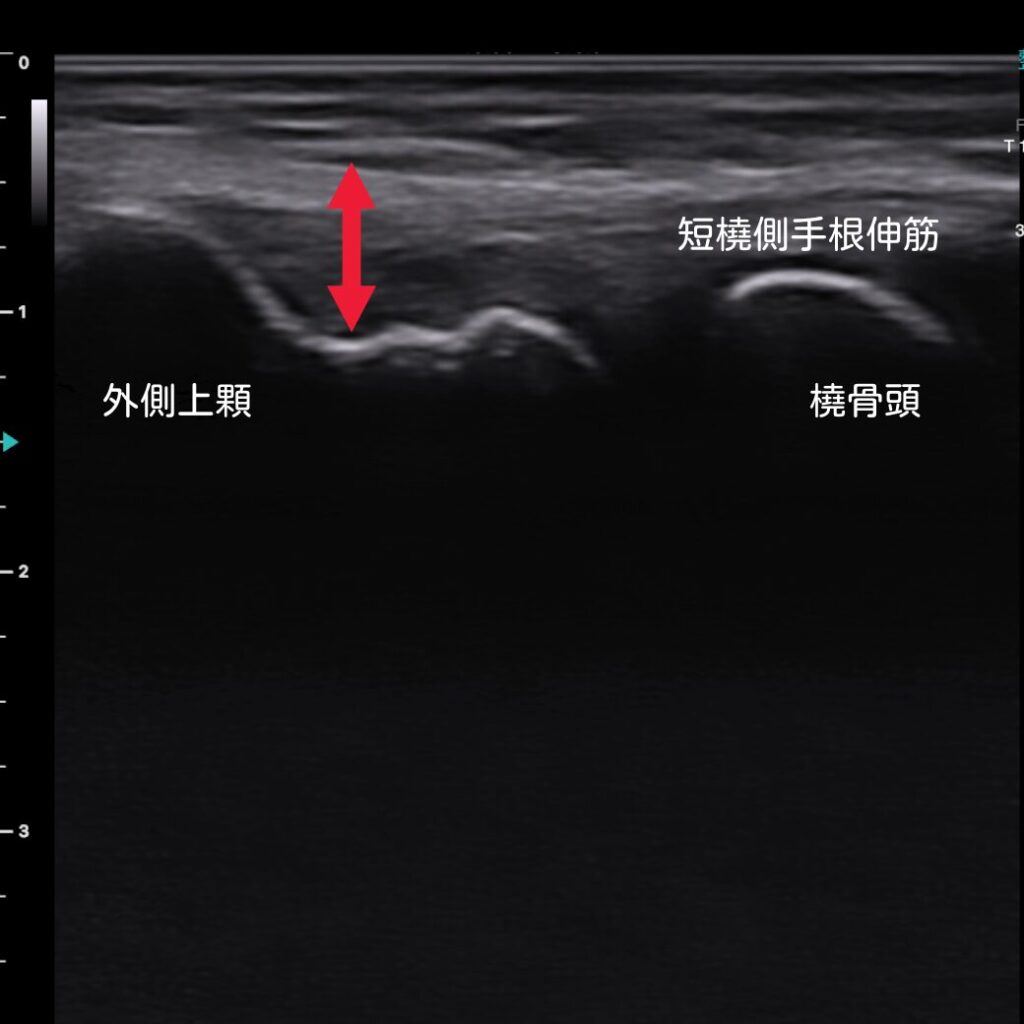

エコーで患部を「見える化」

当院では、超音波エコーを活用し、腱の付着部や肥厚の状態をリアルタイムに左右比較しながら観察できます。これにより、痛みの原因をより正確に把握し、最適な施術プランを立てることが可能になります。

エコー確認で、腱の厚みの違いが明らかになります。合わせて炎症状態も確認が可能です。